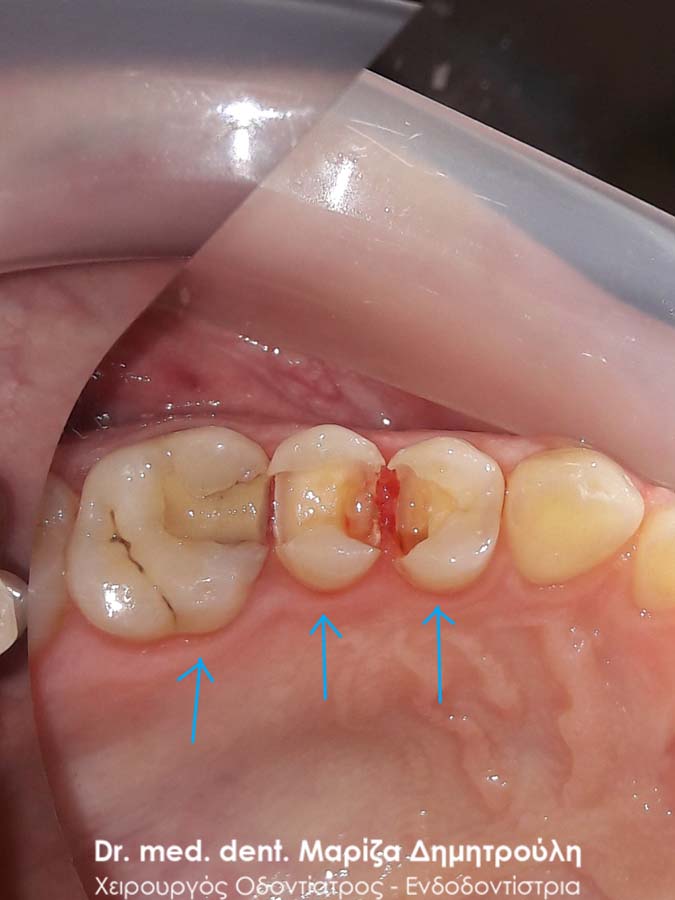

Στα πλαίσια του ετήσιου οδοντιατρικού ελέγχου εντοπίστηκε ένα τερηδονισμένο δόντι, το οποίο δεν είχε γίνει αντιληπτό από τον ασθενή. Προτού ξεκινήσει η διαδικασία τροχίσματος του δοντιού, ο ασθενής ενημερώθηκε οτι η τερηδόνα πιθανόν να εκτείνεται βαθιά (στο ύψος του νεύρου του δοντιού), γεγονός που επιβεβαιώθηκε κατά τη διάνοιξη της κοιλότητας (2η φωτογραφία). Η αποκατάσταση του δοντιού πραγματοποιήθηκε με λευκό σφράγισμα ρητίνης.

ΠΡΙΝ

Εικόνα της βαθιάς τερηδονικής κοιλότητας του δοντιού

ΜΕΤΑ